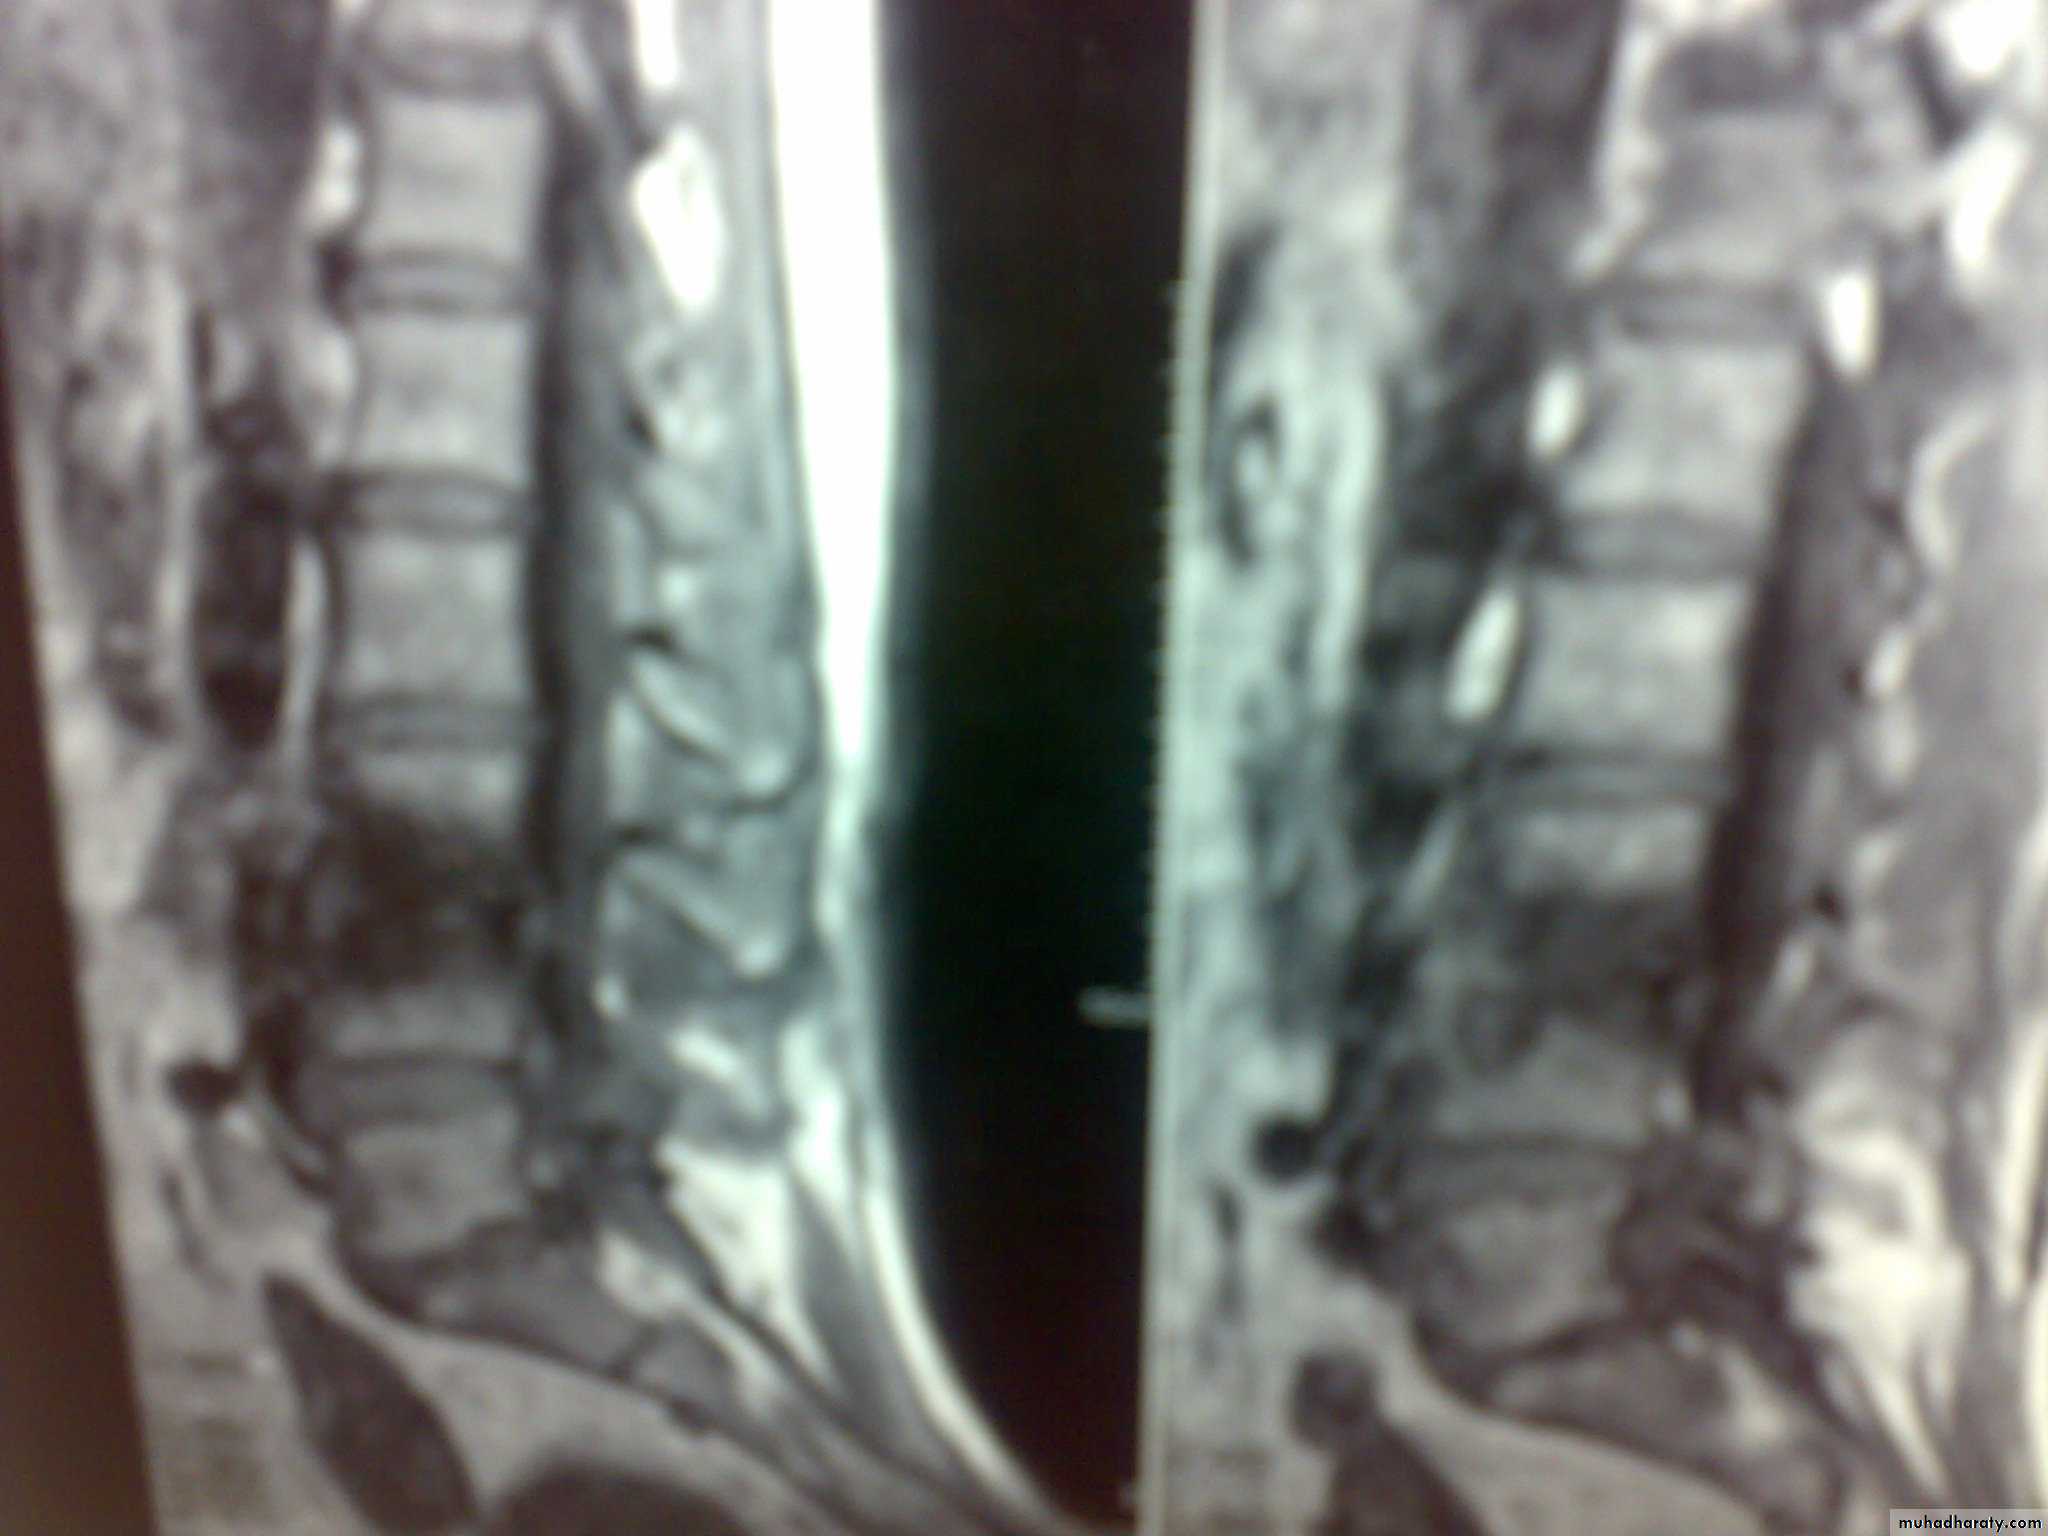

Discitis is an inflammation of the vertebral disc space often related to infection. Infection of the disc space must be considered with vertebral osteomyelitis, as these conditions are almost always present together and share much of the same pathophysiology, symptoms, and treatment. The lumbar region is most commonly affected, followed by the cervical spine and, lastly, the thoracic spineMRI with contrast before 1m.

MRI

Focal features are present in the majority of patients. 1-Musculoskeletal pain in the peripheral and axial skeleton (40 % of cases). 2-Discitis: more commonly involvesthe lumbar and lower thoracic vertebrae .-3-Septic arthritis:commonly affected the knee, hip,& sacroiliac joints, and the pattern either monoarthritis or polyarthritis.4-Osteomyelitis may also accompany septic arthritis.

INFECTIVE DISCITIS